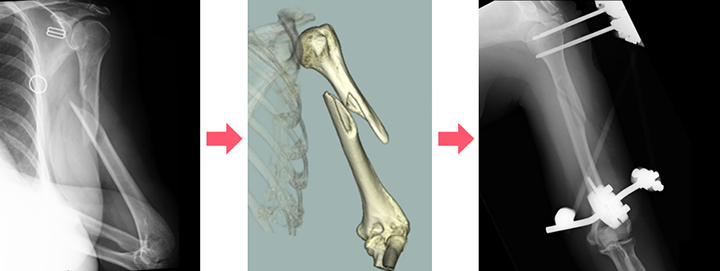

検査・診断

まずはレントゲン写真を撮ります。必要に応じてCT検査も行います。 医師はそれらに加えて、神経や血管の損傷がないかを確認します。指がつめたい、動脈が触れないといった血管の損傷が疑われるときは超音波検査や造影剤を用いた検査を行うことがあります。これらをもとに治療方針を決定します。

プレート固定や髄内釘(芯棒を入れる)固定などの手術療法があります。 どのような手術方法が良いかは骨折の場所や状態などを見て判断します。 粉砕骨折や軟部組織の損傷が激しい開放性骨折など、様々な理由ですぐにプレート固定や髄内釘固定手術が行えず、本番の手術までに待機期間を要する場合は、骨折部の上下に経皮的に骨にピンを刺入して体外でロッドを用いて連結させて骨折部を安定化させる創外固定という手術を応急的に行う場合もあります。手術は全身麻酔で行われることが多く入院が必要になります。

プレート固定

創外固定